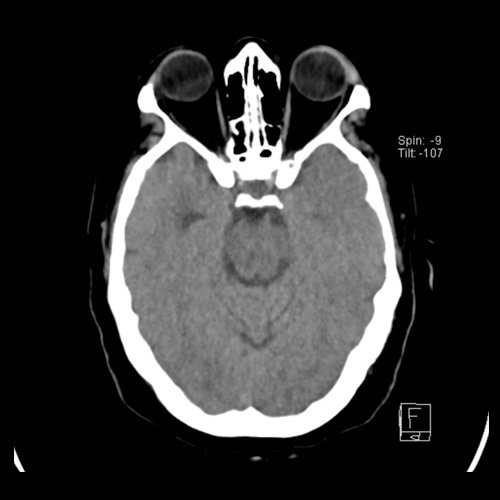

Tomografía de craneo con contraste EV (10/02/26): El parénquima cerebral no pone en evidencia alteraciones densitométricas. No se observan procesos expansivos. El sistema ventrículo-cisternal es de forma, tamaño y situación normales. No se observan signos de sangrado intra ni extra axial. Línea media conservada. El cuarto ventrículo es de forma, tamaño y situación habituales. No se identifican alteraciones densitométricas en los hemisferios cerebelosos. La calota craneana es de aspecto conservado. No se observaron refuerzos patológicos tras la administración de contraste EV. Si la clínica lo amerita complementar con RMI

Tomografia de craneo con contraste endovenoso (10/02/2026) Corte axial: sin alteraciones a nivel selar.